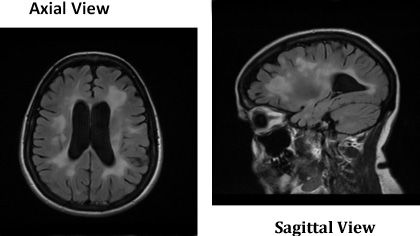

Diffusion tensor MRI tractography studies typically show diffusivity abnormalities in MS patients that are not seen in controls and that correlate with various measures of clinical severity. Here, the technology was used to reconstruct white matter tracts in healthy control subjects. On the top row are the corpus callosum, fornix, and inferior fronto-occipital fasciculus; on the bottom, the uncinate, arcuate, and cingulum fasciculus. Hard exudates composed of lipid and protein deposits are seen and a cotton-wool spot (nerve fiber layer infarct) is also visible.

Image courtesy of Massimo Filippi